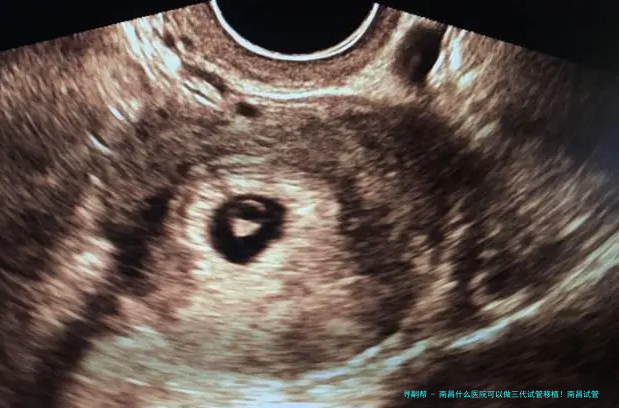

三代试管移植技术是辅助生殖技术中的先进手段,主要用于解决精子健康状况差、卵子质量问题以及遗传性疾病等方面的生育难题。 通过严格的胚胎检查筛选和遗传检测,可以提高成功率,同时减少因遗传不足导致的子孙健康风险。 三代试管移植技术的使用为许许多多家庭提供了生育希望。

1. 宫颈扩张: 医生会使用仪器将子宫颈扩张,以便胚胎顺利进入子宫腔内。2. 胚胎移植: 将选择好的胚胎通过细长管导入子宫内。整个过程只需几分钟时间。3. 观察和监测: 移植后,需要定期进行孕激素水平监测,确保胚胎着床成功。总结